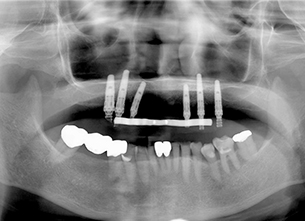

症例1 : 上下顎無菌顎症例

69歳、男性。

• 上顎は両側サイナスリフトと同時に即時荷重を行った。

• 下顎は抜歯即時埋入即時荷重を行った。

• 最終補綴物は、チタンのP.I.B.とM.B.のコンビネーションで修復した。

• 本症例の要旨は第39回日本口腔インプラント学会(大阪)にて症例報告した。